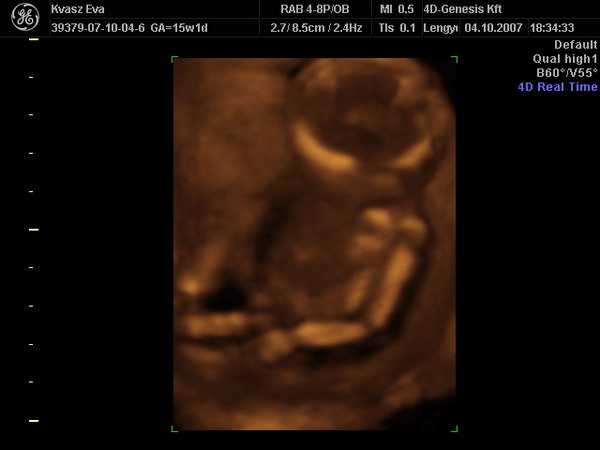

Megérkeztünk a 4D-ről.

Hát, ennyit a megérzéseimről. :cry: A gyermek egyértelműen megmutatta, hogy márpedig ő nem lesz Zsófi. Apa majd kiugrott a bőréből. Ezek szerint ő is fiúpárti. :roll: Mostantól én sem panaszkodhatom arra, hogy nincs bennem fütykös. :lol: :lol: :lol: :lol: :lol:

Mindjárt próbálok képet is feltenni, mert az összeset megkaptuk cd-n.

LEXA!!!!! Ha előkerültél írd be a táblázatba légyszíves, hogy Botondunk lesz. :lol:

Az első képen jól nézzétek meg a lábam közét!!! :lol: :lol: :lol: :lol: :lol: :lol: :lol:

Irigyellek, h ilyen mázlitok volt, h ilyen szép képeket sikerült készíteni. Ez azért ritka ilyen fiatal terhességnél..

Az első uh kép, olyan mint egy Leonardo rajz.

Gyönyörű ez a gyerek. Gratula hozzá!!! :lol:

Évi! Annyira gyönyörű az a 4D-s kép! Nagyon tetszik! Már én is alig várom, hogy menjünk. Neked hol csinálták? Gyűjtöm az infókat, hova érdemes menni, mert ami nekünk legközelebb lenne ( a szegedi) azt nagyon nem ajánlották...

Xien, mi Bp- voltunk a 4D Genesisben, de gondolom az neked kissé messze van. Bár, ha jössz a talira... :wink: